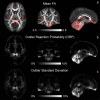

The goal of this study is to characterize the potential effect of artifacts originating from physiological noise on statistical analysis of diffusion tensor MRI (DTI) data in a population. DTI derived quantities including mean diffusivity (Trace(D)), fractional anisotropy (FA), and principal eigenvector (ε(1)) are computed in the brain of 40 healthy subjects from tensors estimated using two different methods: conventional nonlinear least-squares, and robust fitting (RESTORE). RESTORE identifies artifactual data points as outliers and excludes them on a voxel-by-voxel basis. We found that outlier data points are localized in specific spatial clusters in the population, indicating a consistency in brain regions affected across subjects. In brain parenchyma RESTORE slightly reduces inter-subject variance of FA and Trace(D). The dominant effect of artifacts, however, is bias. Voxel-wise analysis indicates that inclusion of outlier data points results in clusters of under- and over-estimation of FA, while Trace(D) is always over-estimated. Removing outliers affects ε(1) mostly in low anisotropy regions. It was found that brain regions known to be affected by cardiac pulsation - cerebellum and genu of the corpus callosum, as well as regions not previously reported, splenium of the corpus callosum-show significant effects in the population analysis. It is generally assumed that statistical properties of DTI data are homogenous across the brain. This assumption does not appear to be valid based on these results. The use of RESTORE can lead to a more accurate evaluation of a population, and help reduce spurious findings that may occur due to artifacts in DTI data.